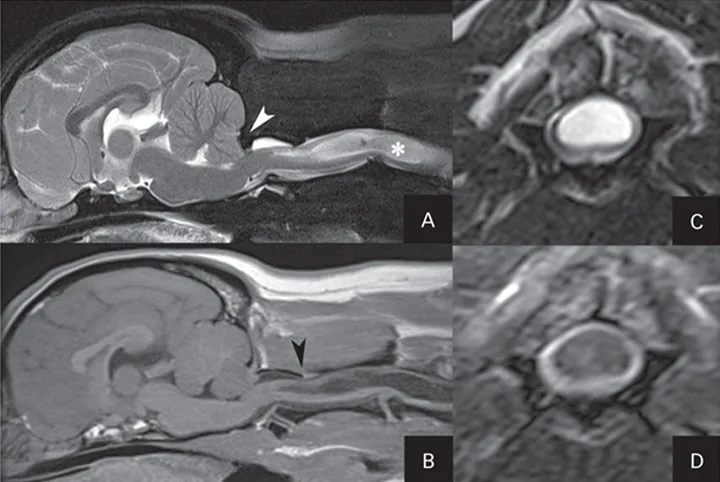

Sagittal and transverse MRI of the brain and cranial cervical spinal cord. Midline sagittal T2-weighted fat saturated MRI image (A)—white arrow indicates compression and coning of the cerebellum because of dysplastic occipital bone, and white star is located within a well-demarcated, T2-hyperintense (bright) lesion that likely represents syringohydromyelia (SHM). Midline sagittal T1-weighted MRI image (B)—black arrowhead indicates interarcuate ligament hypertrophy causing dorsal spinal cord compression at the C1-C2 vertebral articulation. Transverse T2-weighted MRI at the level of the C3 vertebra (C), displaying the extent of the SHM lesion within the spinal cord. Transverse T2 fluid-attenuated inversion recovery (FLAIR)-weighted MRI at the same level (D); the hyperintense spinal cord lesion seen is now hypointense, indicating cerebrospinal-like fluid.

A T2 hyperintense–T1 hypointense lesion within the spinal cord parenchyma from the level of C1 caudally was noted. The tympanic bullae contained T2-hyperintense and T1-isointense material. No contrast enhancement was identified (Figures 1 and 2).